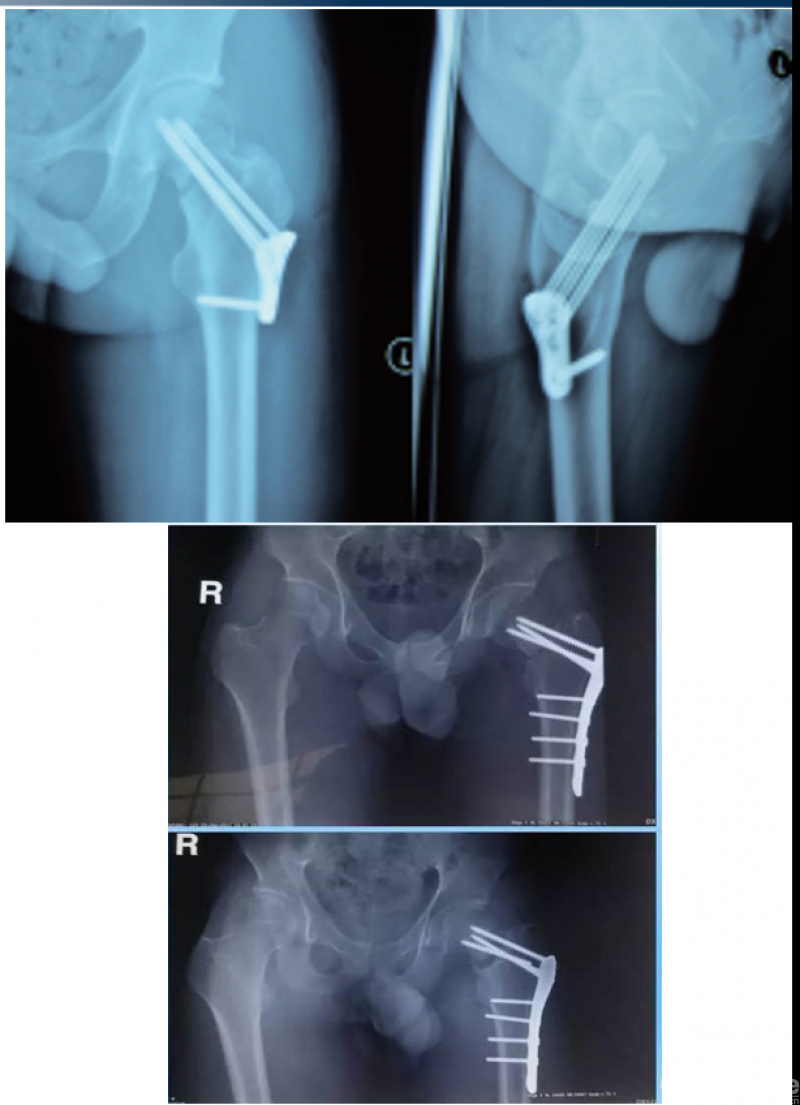

影像学资料

诊断:股骨颈基底部骨折(Garden III)并转子间骨折

初次治疗:切开复位锁定钢板内固定

术后影像资料(2021.9.21)

骨折术后骨不连(2022.3)

骨折术后骨不连(2022.7.3)